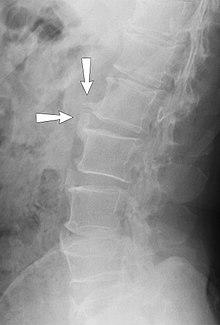

X-ray showing osteophytes of spondylosis of the lumbar spine.

A range of bone-formation processes are associated with aging, degeneration, mechanical instability, and disease (such as diffuse idiopathic skeletal hyperostosis). Osteophyte formation has classically been related to sequential and consequential changes in such processes. Often osteophytes form in osteoarthritic joints as a result of damage and wear from inflammation. Calcification and new bone formation can also occur in response to mechanical damage in joints.[5]